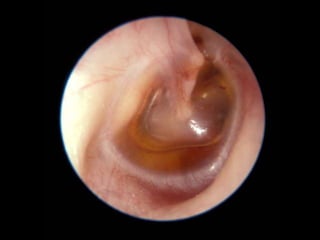

The Tympanic Cavity

CERUMEN CAST

OTOSCLEROSIS